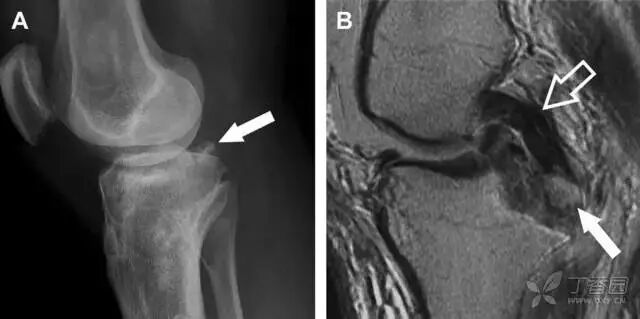

股骨外侧髁凹陷征(图 2)

图 2 扭伤后的股骨外侧髁凹陷征。A 侧位片示股骨外侧髁凹陷。B MRI 矢状位 T2 加权像示股骨外侧髁及胫骨后外侧骨挫伤(空箭头)。胫骨近端随着后交叉韧带撕裂发生移位,露出外侧半月板的后角(弧形箭头)